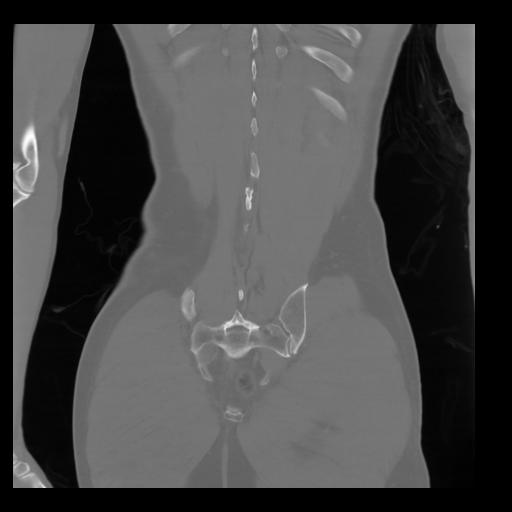

35 CUERPO,CE,Coronal,3.000,CUERPO,Coronal,